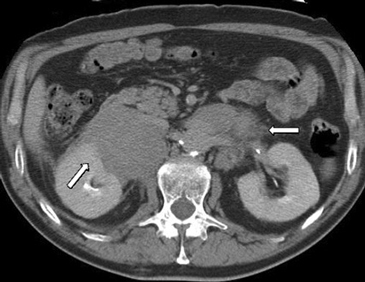

En la TC no contrastada las glándulas suprarrenales normales son homogéneas y simétricas, con una densidad muy similar a la del parénquima renal adyacente (Figura 1 a). Con un medio de contraste ev la glándula suprarrenal se opacifica en forma homogénea, similar al hígado o al bazo (Figura 1 b). Si la cantidad de tejido adiposo retroperitoneal es abundante las glándulas suprarrenales pueden aparecer enteramente rodeadas por grasa y su delimitación es más fácil (Figura 2 a); lo inverso ocurre en pacientes muy delgados con escasa grasa retroperitoneal (Figura 2 b). En RM, en secuencias ponderadas en T1 y T2 convencionales tienen una intensidad de señal homogénea, hipointensa respecto de la grasa adyacente e iso o hipointensa con respecto del parénquima hepático (Figura 3 a y b). En los cortes coronales se aprecia mejor la forma y la posición de las glándulas suprarrenales (Figura 3 c).

Figura 3. Glándula suprarrenal normal en resonancia magnética. (a) Cortes axial ponderado en T1 la señal de la glándula normal (flecha negra) es hipointensa respecto a la grasa retroperitoneal e isointensa respecto al parénquima hepático. (b) Cortes axial ponderado en T2 en que se muestra la glándula suprarrenal derecha (flecha blanca) y (c) corte coronal ponderado en T2 en que se muestra la glándula suprarrenal derecha (flecha blanca) y la glándula suprarrenal izquierda (flecha negra) con similares características de intendidad de señal. 3. Causas y prevalencia de las lesiones suprarrenales